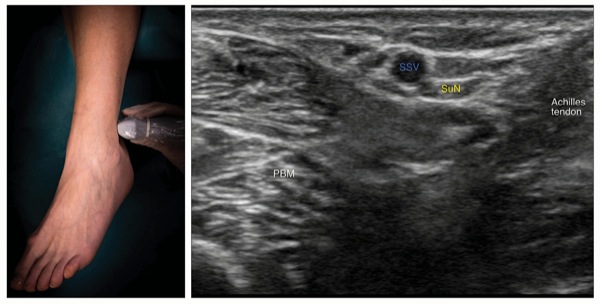

To Block the Sural Nerve

Place the transducer in a transverse orientation between the lateral malleolus and the Achilles tendon (Figure 7).

Identify the small saphenous vein superficial to the deep fascia and the sural nerve, which is a small hyperechoic structure next to it. The nerve may not always be seen.

Insert the needle using an in-plane or out-of-plane approach underneath the deep fascia (Figure 8).

Inject 1 to 2 mL of local anesthetic to confirm proper needle positioning by observing the spread around the small saphenous vein.

Complete the block with a volume of 3 to 5 mL.